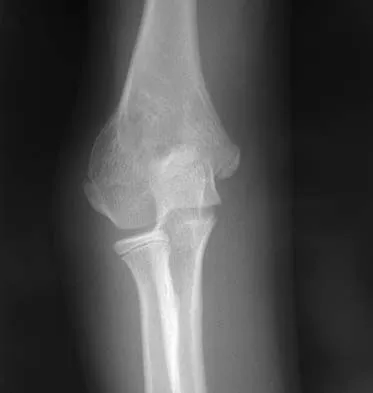

Figure 38 shows the radiograph of a 16-year-old wrestler who injured his elbow when he was thrown to the mat by his opponent. To minimize additional trauma to the medial soft tissues, the elbow should be reduced in

Explanation